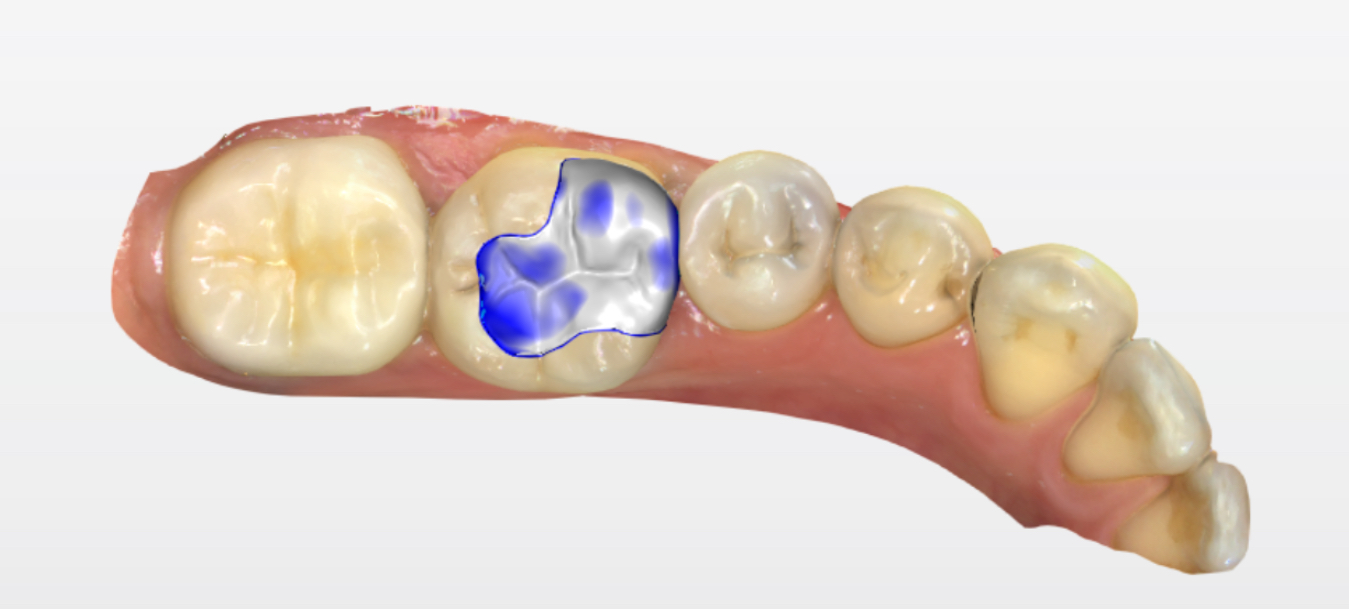

嵌体修复是一种精准的修复方式,特别适合像患者这样龋坏较深但无需根管治疗的情况。该患者选择了西诺德全瓷嵌体修复,去龋坏,IROOT-BP间接盖髓+光固化玻璃离子+3M流动树脂垫底。基牙预备,排龈,精修,然后CEREC扫描,获取牙齿模型,定制出与缺损部位完全匹配的陶瓷嵌体。嵌体制作完成后,医生将其粘接固定在牙齿上,恢复了牙齿的形态和功能。

修复后,患者的牙齿不仅外观自然,咀嚼功能也完全恢复。嵌体修复因其密合性好、耐用性强,能有效防止继发龋的发生。患者表示,嵌体修复不仅解决了他的牙齿问题,还让他更加重视日常口腔护理。